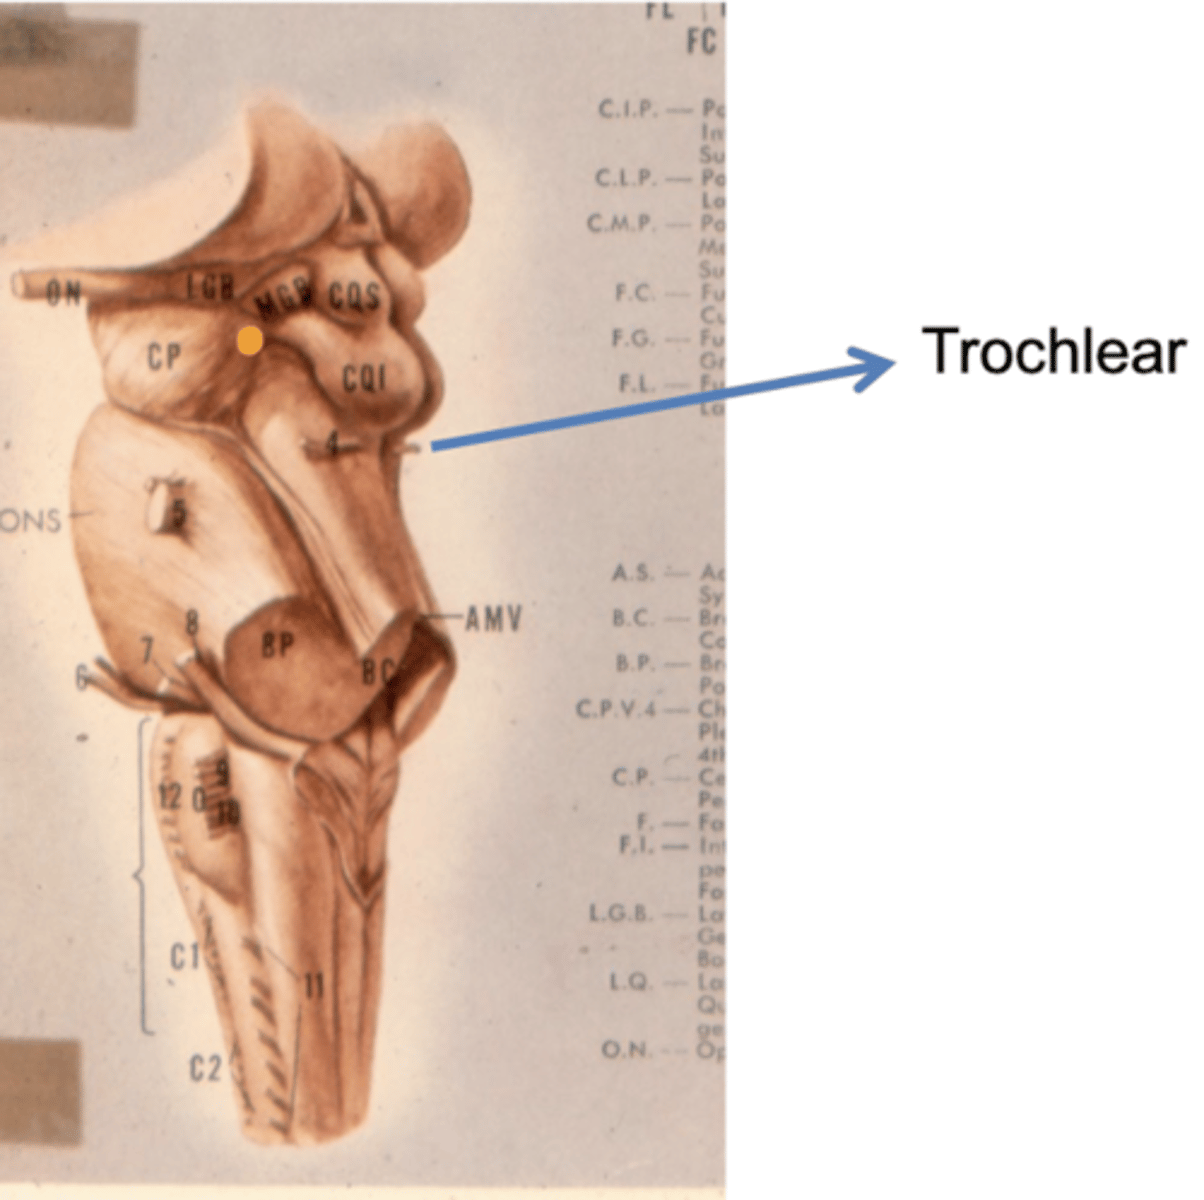

Where does CN IV exit the brainstem?

inferior colliculus (dorsal surface)

exits dorsal + caudal (posteroinferior) to nucleus

What is the superior medullary velum?

membrane that forms the superior portion of the 4th ventricle roof

image -- 7

What is the inferior medullary velum?

membrane that forms the inferior portion of the 4th ventricle roof

image -- 1